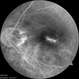

- Myopic neovascularization

- macular hemorrhage, cyst, myopic choroidal neovascularization (CNV)

- The image of right eye of 51-year-old lady with high myopia show " Bow-Tie" macular hemorrhage (A). Optical coherence tomography (B) scan passing through hemorrhage showed intraretinal cystic lesion. During the course of intravitreal anti-VEGF injection treatment, the lesion converted into typical myopic choroidal neovascularization (C).